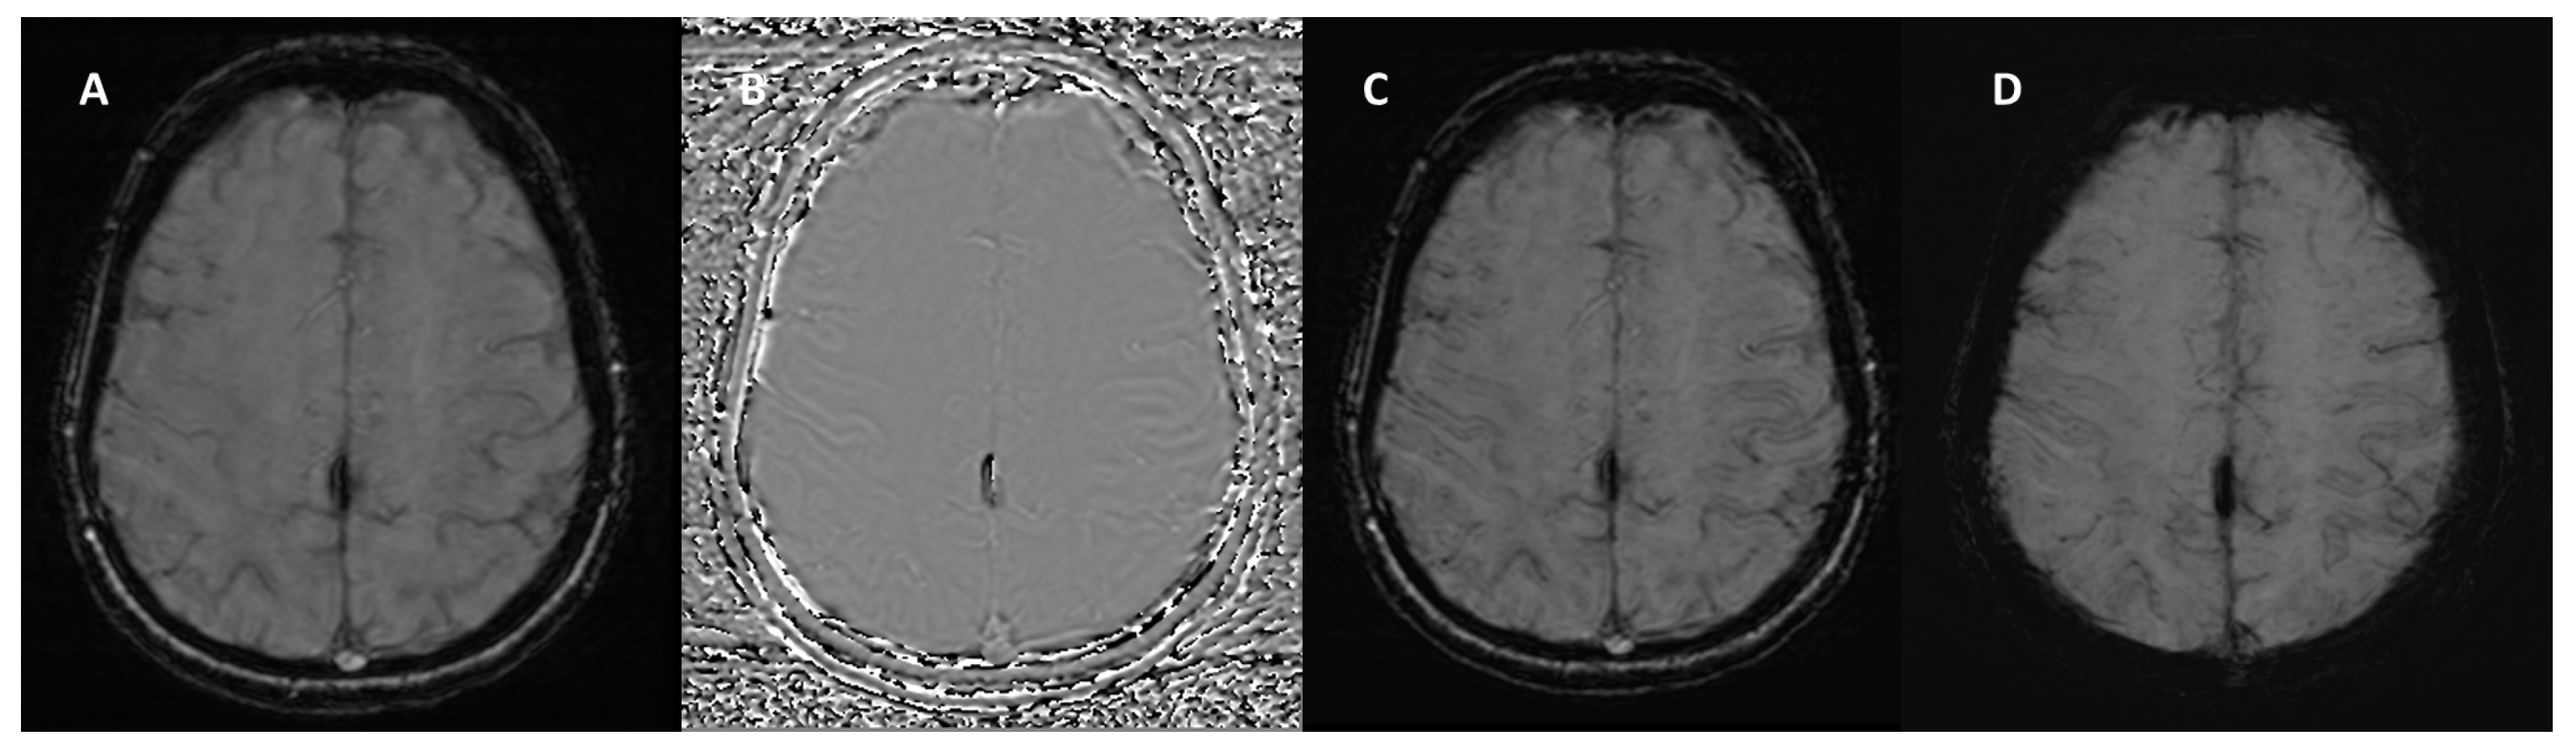

4.2. Multiple Sclerosis

| Multiple sclerosis | Central vein sign | Punctate or linear hypointensity at the center of a hyperintense lesion in at least 2 of 3 orthogonal planes (>2 mm) |

| Paramagnetic rim lesions | Hypointense rim surrounding an internal lesion that is isointense to adjacent normal white matter | |